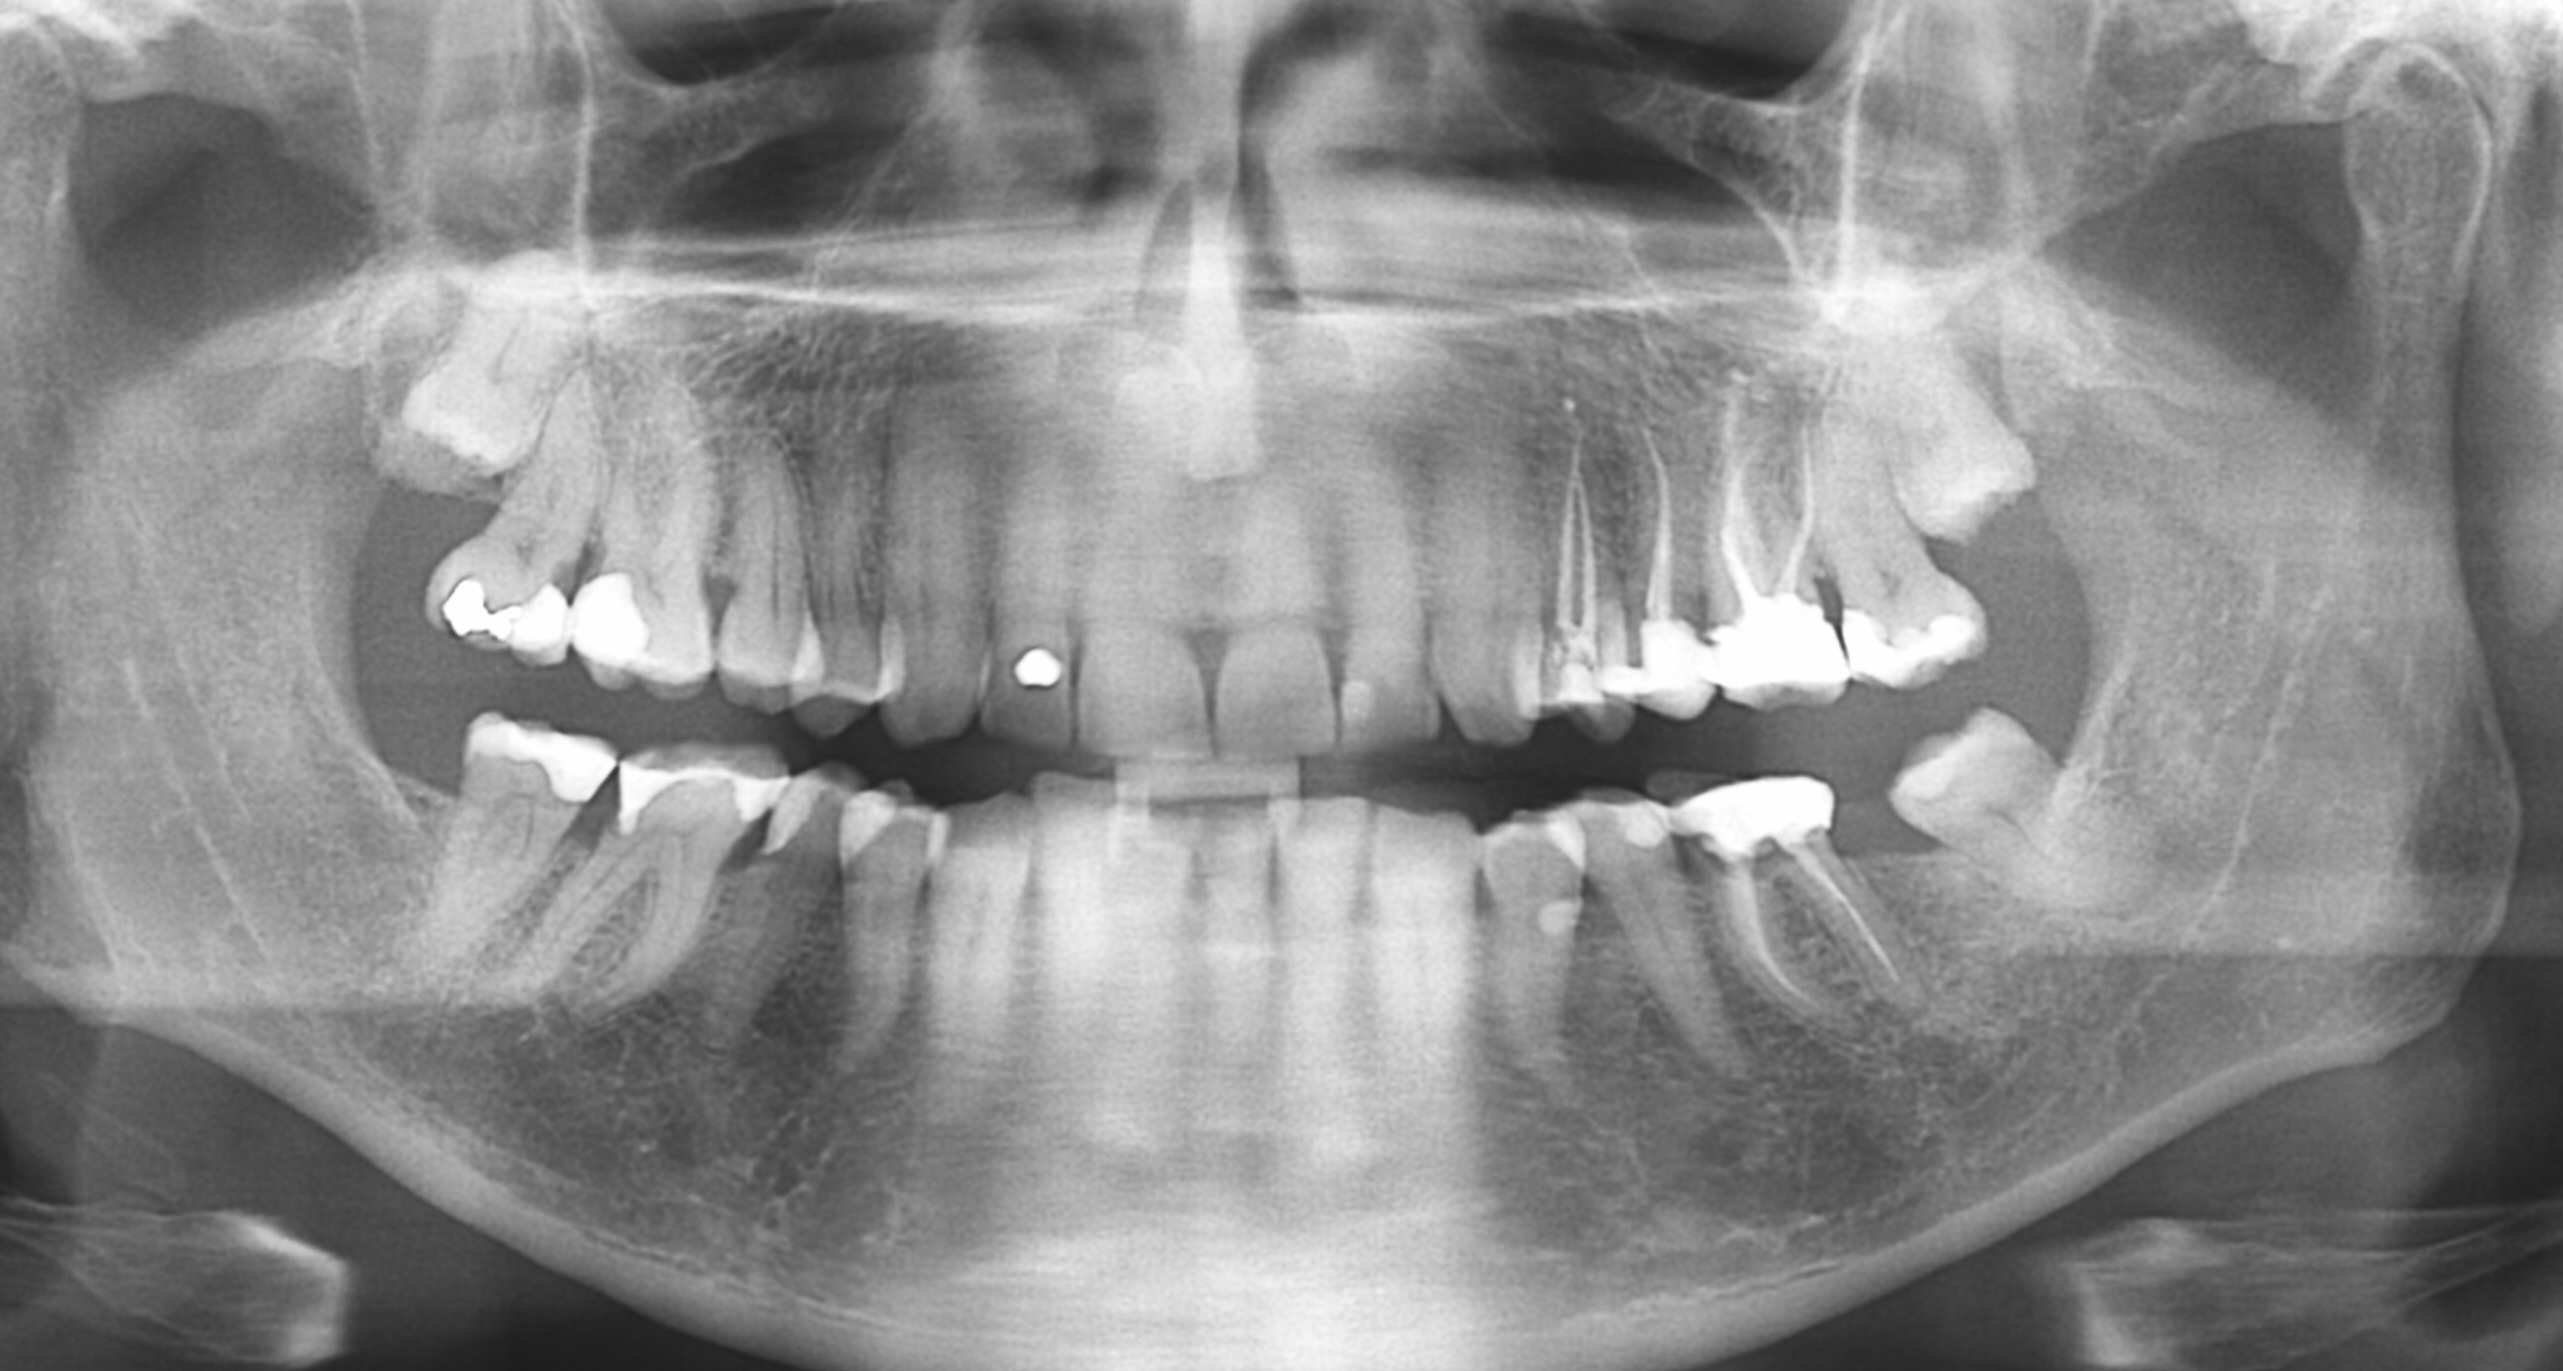

Zou graag de x-foto v d 38 zien. Als 36 getrokken wordt en u geen losse voorziening wil dan kan of een kroon op implantaat of een brug, afhankelijk v d kwaliteit v d buur/pijler elementen, een oplossing zijn. Is de 27 aanwezig??> Zo ja en 36/38 worden getrokken kunt u kiezen voor een of twee implantaten, een minimaal en verkorte tandboog met geen functie v d 27 of twee implantaten. Vraag de x-foto kan ik het beter beoordelen. Is er misschien ook een panorama (OPT) foto.

Op deze foto , lijkt, de 36 op. Bodem tussen de wortels lijkt te dun. Maar pas echt te beoordelen als vulling gesloopt wordt en beoordeeld wordt of het stevig genoeg is om een kroon te maken.. Keuze los ( frame prothese) of vaste voorziening ( brug35-38 of implantaten 36-37.) als vervanging. Maar wat laat u doen met de 14, 15, 16, 17, 46, 47 ....ook bekronen of ook laten gaan en een uitneembare voorziening. Waarom zo lang wachten met kronen ...of is het om financiële redenen. Verder gaten in de 46 distaal en 17 mesiaal. Op deze foto kan ik niet goed beoordelen of er een ontsteking is aan de 38. Zou daar een "kleine" foto v laten maken om dat te beoordelen ( en dan ook de 35 beoordelen, kan op dezelfde foto,daar is een panorama foto niet gedetailleerd genoeg voor. Maak een duidelijk behandel strategie voor de toekomst met uw tandarts. Als men wil/kan, kan voor alles gespaard worden maar helaas zijn er vaak andere uitgaven die prioriteit hebben.

Hangt v behandel plan toekomst af. Waar is voor gekozen. ...Twee implantaten??? dan is 38 niet nodig. Brug wel. En voor een frame zou ik het voorlopig houden. Eerst x-foto om te beoordelen bij behoud. Deze foto is niet altijd duidelijk genoeg. Eerst duidelijk een plan voor de hele mond...dan pas trekken.

Bedankt voor al uw antwoorden. Laatste vraag vooralsnog, is er onder kies 36 welke er maandag in elk geval uitgaat, wel een ontsteking te zien.

Mijn tandarts spreek van "een tikkende tijdbom" rond kies 36 en 38. Dan zou er toch wat te zien moeten zijn op de foto ?

Gaat erom of de kroon goed op de implantaat past> daar zou ik de controle x-foto voor het definitief plaatsen moeten beoordelen. Of is uw bot /tandvlees terug getrokken zodat de implantaat zichtbaar is geworden. Dat kan ik niet uit deze foto opmaken. Geschroefde kroon kan los gedraaid worden.